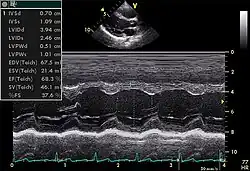

Echocardiogram in the parasternal long-axis view, showing a measurement of the heart's left ventricle

Motion mode, though less commonly used, plays an important role in modern echocardiography. It has an advantage over 2D echocardiography due to its high temporal resolution (up to 1000 frames/sec). Examples of its use include accurate measurement of LV size, assessment for presence of cardiac tamponade, and assessment of RV function with TAPSE (tricuspid annular systolic plane excursion).